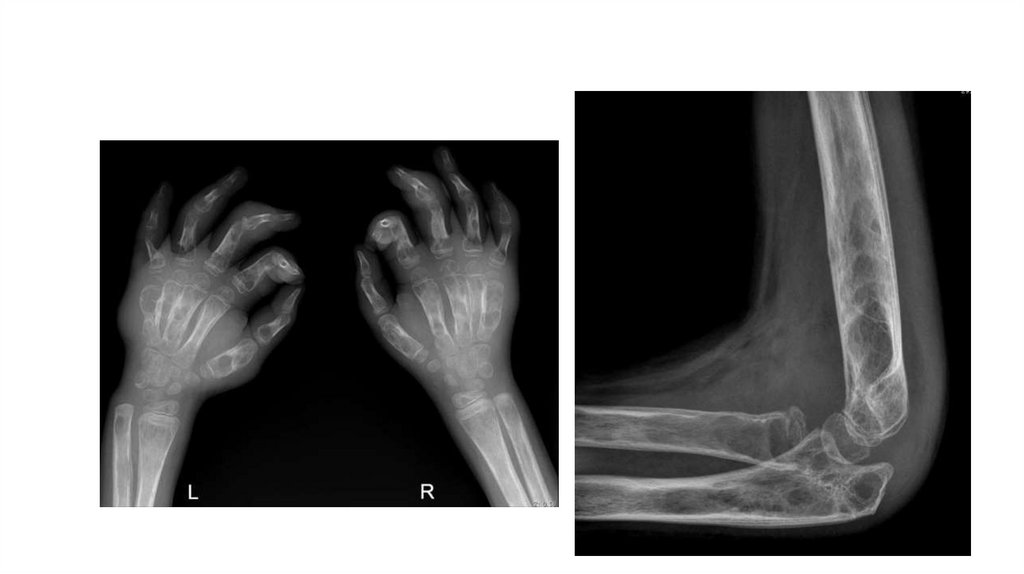

Воспалительные заболевания опорнодвигательного аппарата

«Воспалительные

заболевания опорнодвигательного аппарата»